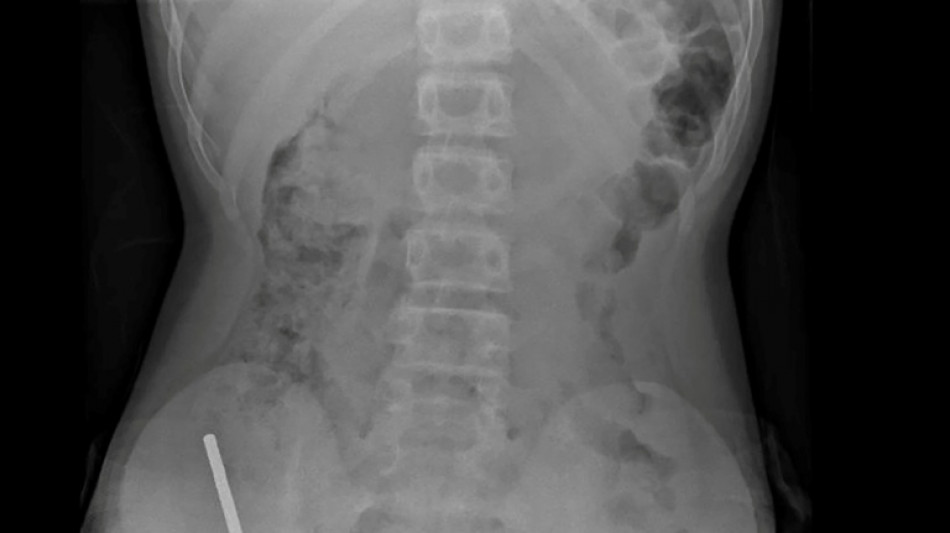

Nouvelle-Zélande: un adolescent opéré après avoir ingéré près de 100 aimants achetés sur Temu / Photo: © NEW ZEALAND MEDICAL JOURNAL (NZMDJ)/AFP

En Nouvelle-Zélande, un adolescent de 13 ans s'est vu retirer plusieurs parties nécrosées de ses intestins après avoir avalé près d'une centaine d'aimants achetés en ligne sur le site Temu, a rapporté vendredi une revue médicale.

Après avoir souffert de douleurs abdominales pendant quatre jours, l'adolescent a été transporté à l'hôpital de Tauranga, sur l'île du Nord.

"Il avoué avoir ingéré entre 80 et 100 aimants puissants au néodyme, de 5x2mm environ, une semaine plus tôt", indique un rapport des médecins de l'hôpital de cet hôpital, publié dans le New Zealand Medical Journal (NZMJ).

Ce type d'aimants, interdit en Nouvelle-Zélande depuis janvier 2013, aurait été acheté sur la plateforme chinoise d'e-commerce Temu.

Les médecins ont déclaré que la pression exercée par les aimants avait provoqué une nécrose dans quatre zones de l'intestin grêle et du gros intestin du garçon.

Il a été opéré afin que l'on lui retire les aimants et les tissus nécrosés, et il a pu rentrer chez lui après huit jours à l'hôpital.